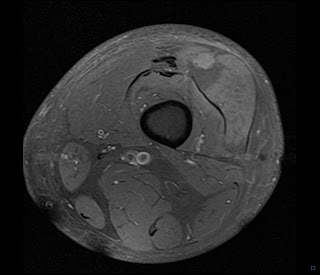

39 male

Sudden onset thigh pain week following hospital admission with septic subacromial/subcoracoid bursitis ( now treated)

However at this visit white cell count , CRP not markedly elevated .

Although not volunteered on requisition form , further enquiry established patient has very poorly controlled/managed Type 2 diabetes mellitus

Diagnosis and discussion follows images

DIAGNOSIS : DIABETIC MYONECROSIS

Occurs in poorly controlled diabetes

Commonly thigh muscles

Sudden onset pain .Lab markers ( CRP, WBC ) typically only mildly deranged

Usually self limiting

Another teaching point is that in my experience, diabetes is often not volunteered on requisition forms for MSK studies but may be very relevant